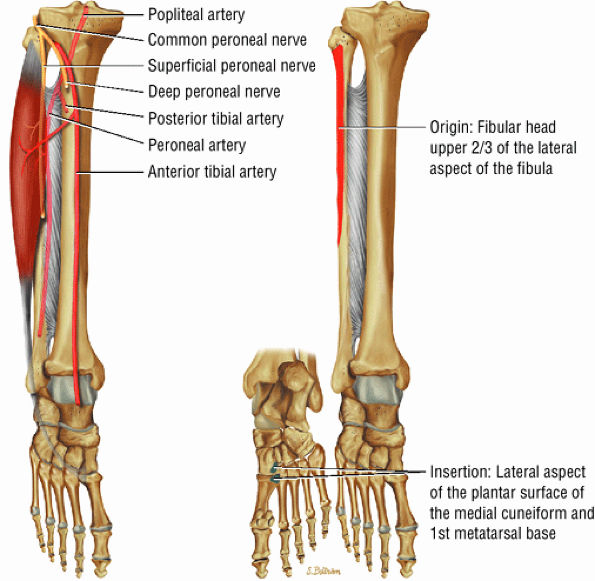

The lateral muscles of the leg are the peroneus longus (Fig. 5.12) and the peroneus brevis (Fig. 5.13).

FIGURE 5.12 ● PERONEUS LONGUS The peroneus longus plantarflexes and everts the foot. The peroneus longus passes underneath the superior peroneal retinaculum, then runs superficial to the calcaneofibular ligament and passes deep to the inferior peroneal retinaculum. The third turn of the peroneus longus occurs as it enters the plantar tunnel between the cuboid and fifth metatarsal base. Ossification of the fibrocartilaginous sesamoid (which protects the tendon as it glides over the cuboid tuberosity) within the peroneus longus occurs in up to 20% of cases.

FIGURE 5.13 ● PERONEUS BREVIS The peroneus brevis plantarflexes and everts the foot. The peroneus brevis has a shorter and smaller muscle belly than the peroneus longus and becomes tendinous 2 to 3 cm proximal to the tip of the lateral malleolus.

The posterior compartment is divided into superficial and deep sections by deep transverse fascia. The superficial posterior compartment consists of the gastrocnemius, the plantaris, and the soleus muscles. The deep posterior compartment contains the popliteus, the FDL, the FHL, and the tibialis posterior muscles. The neurovascular supply is provided by the tibial nerve and posterior tibial artery.

The anterolateral compartment contains the peroneus longus and peroneus brevis muscles. The neurovascular supply is from the superficial peroneal nerve and branches of the peroneal artery.